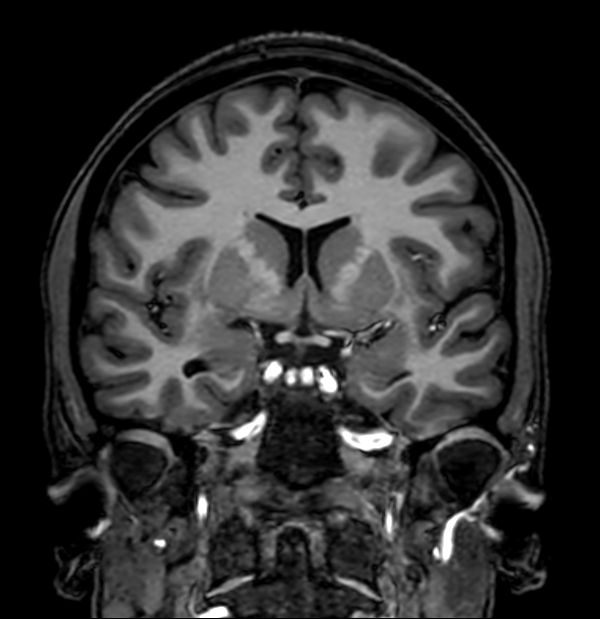

3D T1w TFE (Coronal reformat)

3D Double IR (Coronal reformat)

3D T2w TSE (Coronal reformat)